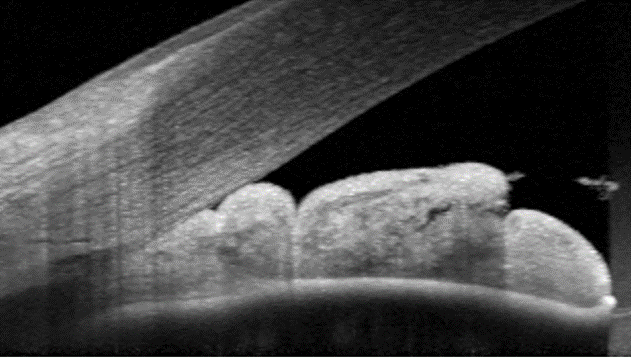

Anterior OCT (right eye)

More info

Anterior OCT (left eye)